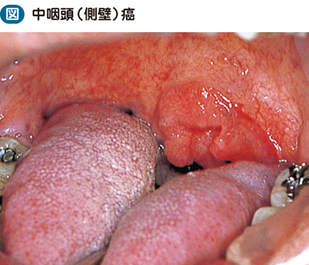

なんかできものができた 中咽頭癌 そして味覚を失った まさぱく